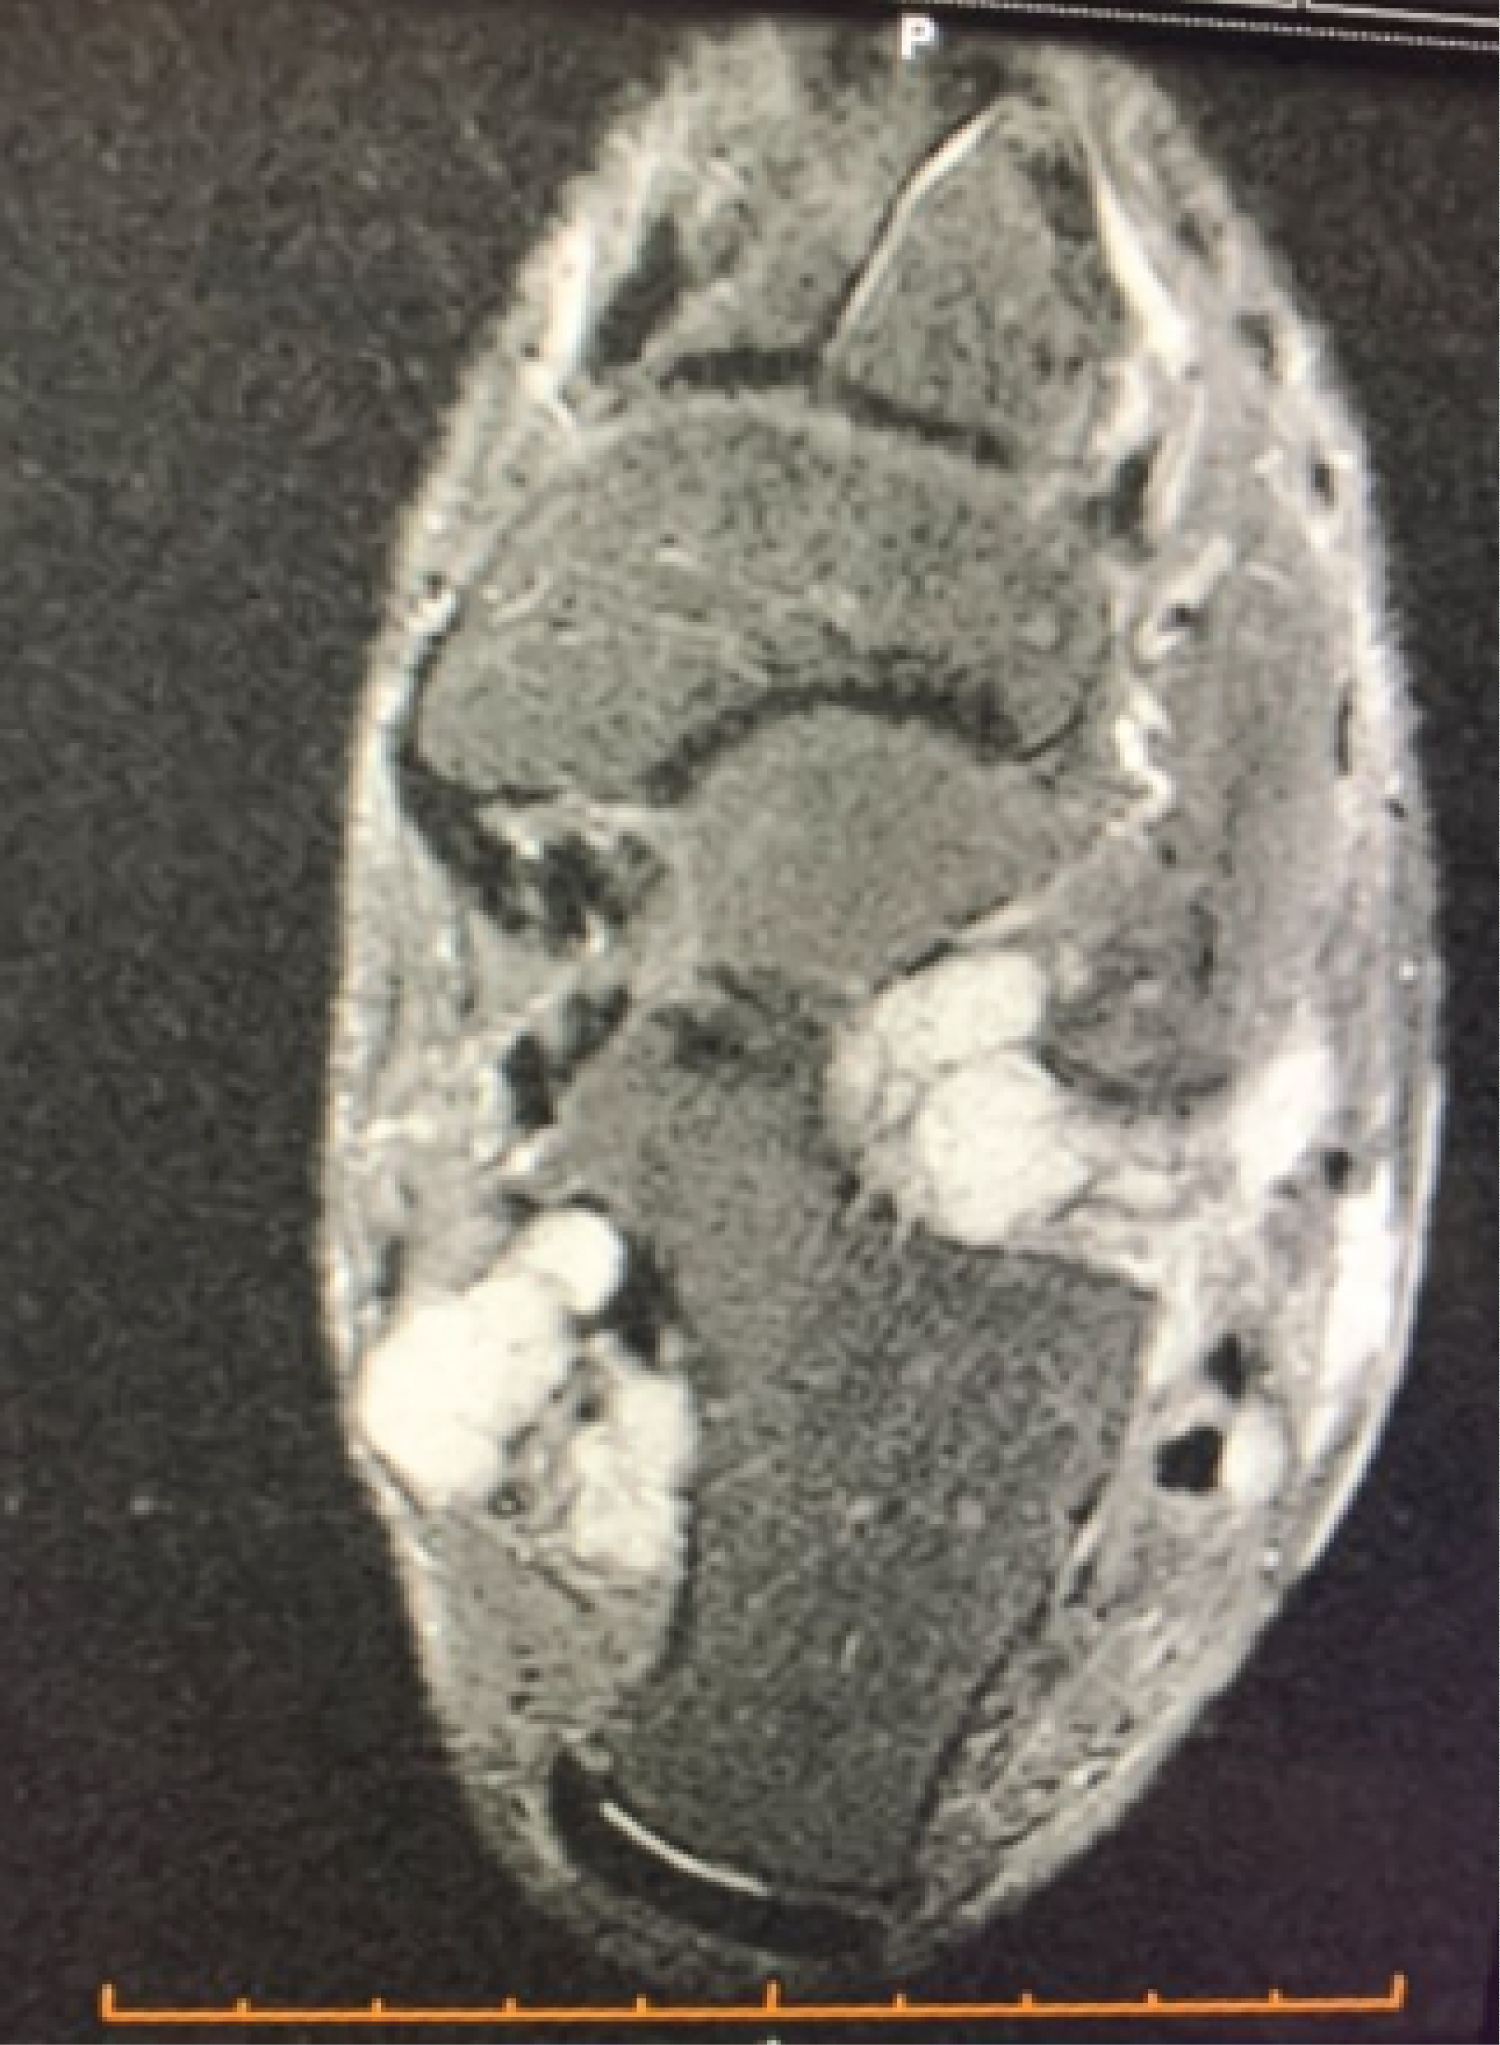

Radiographs revealed an unusual appearance which was reported as being consistent with SC in the ankle. It showed multiple small, calcified bodies surrounding the left ankle joint, there was also a calcified mass noted in the anterior aspect of the distal fibula. A CT Scan was performed, looking at the extent of infiltration of the lesion (Figure 1).

Figure 1: CT scan showing a cartilaginous lesion growing around the ankle joint. View Figure 1